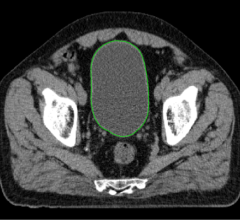

March 2, 2021 — West Virginia University scientists used magnetic resonance imaging (MRI) scans to show what happens ...